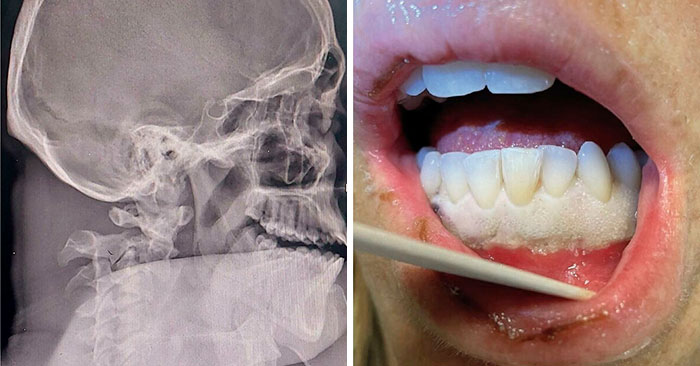

#4 This Is How Great Surgery Has Evolved! Here You Can See The Result Of An Underbite Surgery And Jaw Positioning Correction